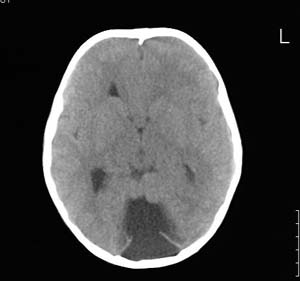

以下是引用lixi在2006-12-5 21:06:00的发言:[br]1、dandy-walker变异。2、胼胝体发育不良。

以下是引用zhuoshandiao在2006-12-5 21:41:00的发言:[br]胼胝体发育不良应该是肯定的。另外考虑dand-walker畸形。

以下是引用卜一在2006-12-5 22:30:00的发言:[br]支持考虑:1、dandy-walker变异。2、胼胝体发育不良